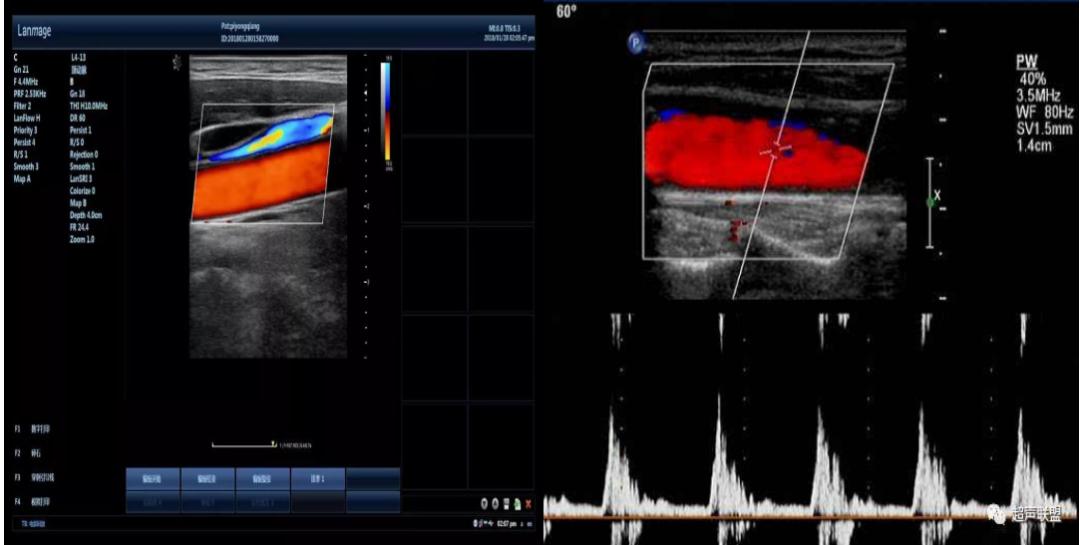

彩超即彩色多普勒血流显像,英文缩写是CDFI,简单来说,彩超是高清晰的黑白B超再加上彩色多普勒,是一种复合图像,就是将所获得的多普勒信息进行处理,通过彩色灰阶编码,以不同的颜色和亮度分别标识血流的方向和速度以及性质,并叠加于B型超声声像图上。

彩超血流的特点是颜色代表血流的方向,即红色代表血流方向朝向探头,蓝色代表血流方向背离探头;色调的亮度表示速度,即色调的亮度越亮表示速度越高,色调的亮度越暗表示速度越低;血流颜色的单纯代表是层流,是正常的血流。五彩镶嵌的花色血流信号代表是湍流或涡流,说明血流性质有改变,多见于狭窄处的血流以及返流。

2.可以动态显示血流的运行方向,方便了解血流的时相和速度。

3.可以辨别动脉和静脉血管,可识别血管性病变和非血管性病变

,可以了解血管的性质,可进一步鉴别良恶性肿瘤有帮助。